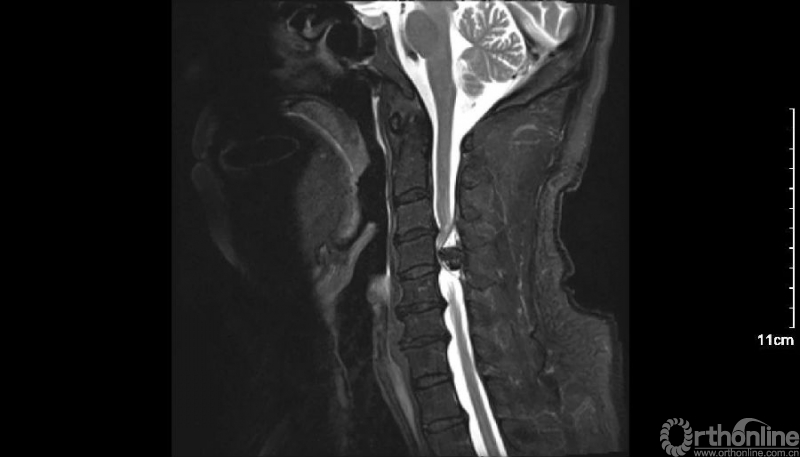

入院查体患者四肢肌张力高,双侧hoffman阳性。CT及MRI检查提示C4/5左侧关节突内缘有一巨大骨块(15mm*16mm),相应节段椎管严重狭窄。椎管内骨块的前端还有一游离骨块。

影像学资料